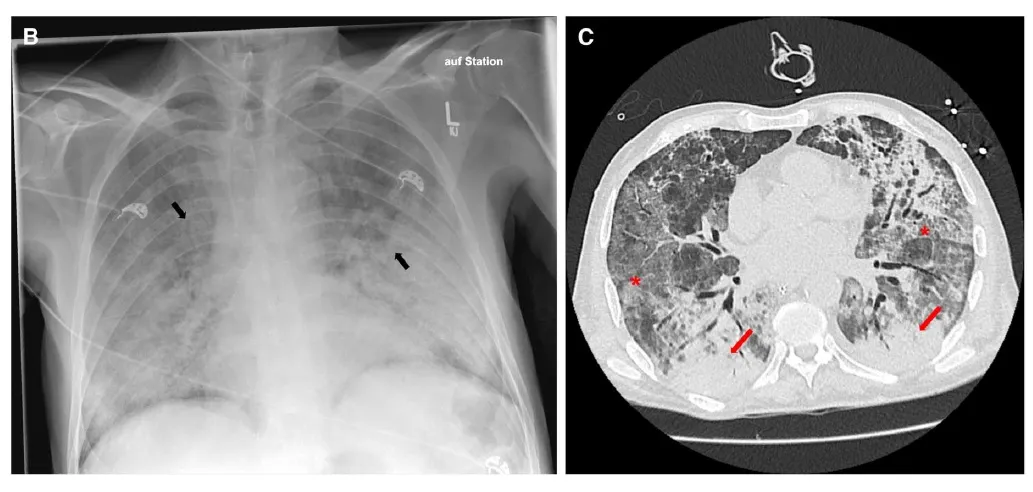

IRA + Icterícia: Um Caso que Exige Investigação Detalhada

IRA + Icterícia: Um Caso que Exige Investigação Detalhada